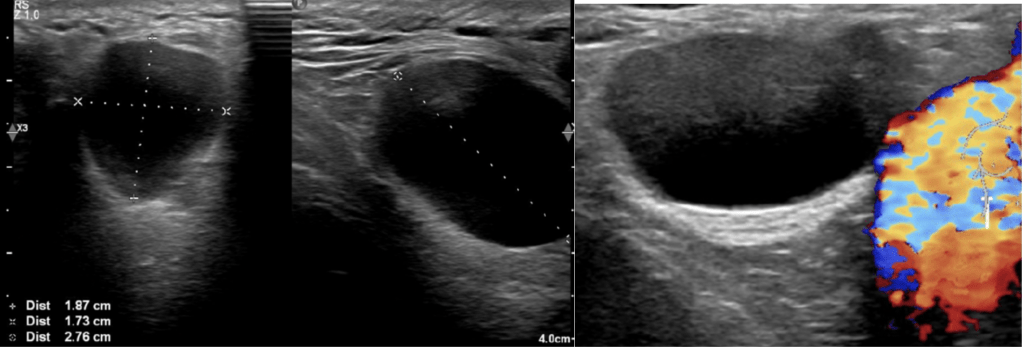

A novel use of Intracavity and intravenous CEUS: The delineation of hepatic abscess formation and conformation of catheter placement. [May 2019]